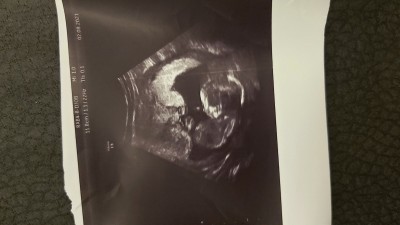

sordu

kizlar şuan 15 haftadayim ilk foto 2 gün önceki ultrason doktor kız net demisti ikisinde de ama ben nedense erkek istedigim icin mi bilmiyorum kız gibi hissedemiyorum bi türlü bide siz bakar mısınız tecrubelerinize dayanarak :))

İkinci fotoğraftaki kız benim de kızım olacak ultrason görüntüsü böyleydi